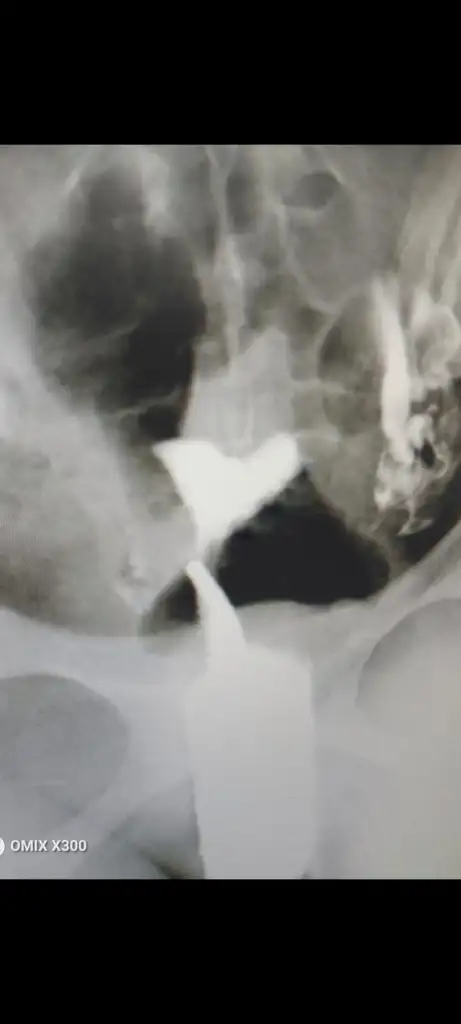

Bu şekilde benimki sizinde boylemiydi

Benim bu şekilde üst taraf tam kalp şekli ama alan yeterli dediler blemiyorm artk,tek doktorlada kalmadm hepsi aynısını dedi ameliyatı varms ama arcuat digerlerine göre riskliyms bende hc doğum yapmadgm için göze alamadm daha doğrusu düsünüyodum ama hamile kaldm

Eklentiler

• Screenshot_20230618-011549.webp

Screenshot_20230618-011549.webp

7,5 KB · Görüntüleme: 101